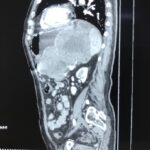

Վիրաբուժության կլինիկայի ղեկավար, պրոֆեսոր Սուրեն Ստեփանյանի կողմից իրականացվել է հերթական բարդ վիրահատությունը. հեռացվել է ստամոքսի հսկա ուռուցք, որը տարածված էր որովայնի վերին հարկում: Հիվանդի նախավիրահատական հետազոտություններից և նախապատրաստությունից հետո, վիրաբույժների թիմը (պրոֆ. Ս. Ստեփանյան, Հ.Սաֆարյան, Վ. Մանվելյան) իրականացրել է վիրահատություն ընդհանուր անզգայացման տակ (անեսթեզիոլոգ Ա. Ղազարյան): Վիրահատության ժամանակ ռևիզիայով պարզվել է, որ ստամոքսի ուռուցքը սերտ կպած էր փայծաղին, ընդգրկել էր ենթաստամոքսային գեղձի պոչի շրջանը և փայծաղի անոթները:

Ուռուցքի հեռացման համար կատարվել է ստամոքսի պատի ծավալուն մասնահատում, ենթաստամոքսային գեղձի դիստալ մասնահատում, փայծաղի հեռացում, խոլեցիստէկտոմիա: Նշված հյուսվածքները հեռացվել են մեկ բլոկով: Հեռացված մակրոպրեպարատի չափերն էին 35սմх25սմх15սմ: